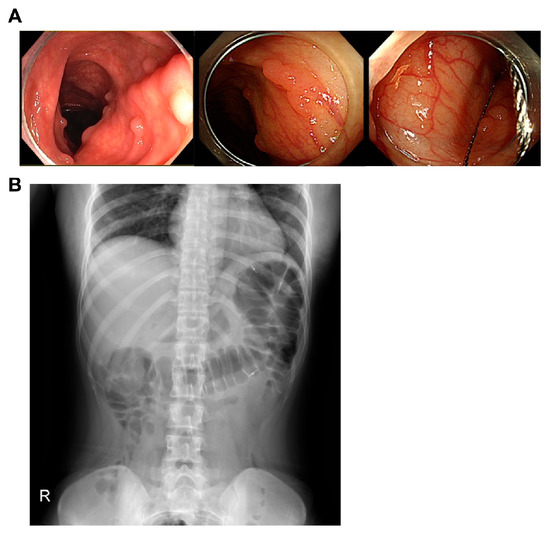

2. Case Report